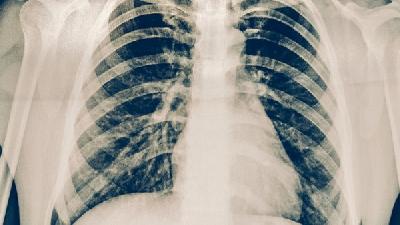

现在有患有肺气肿的非常多,肺气肿系终末细支气管远端部分过度膨胀,并伴有气腔壁的破坏,肺气肿怎样治疗呢?患者们经常会问:有没有好的偏方治疗肺气肿呢?那么今天我们就来看看肺气肿的治疗偏方大全涉及哪些偏方呢?

肺气肿可能由长期吸烟、空气污染、职业粉尘接触、遗传性α-1抗胰蛋白酶缺乏等原因引起,需通过肺功能检查、胸部影像学...